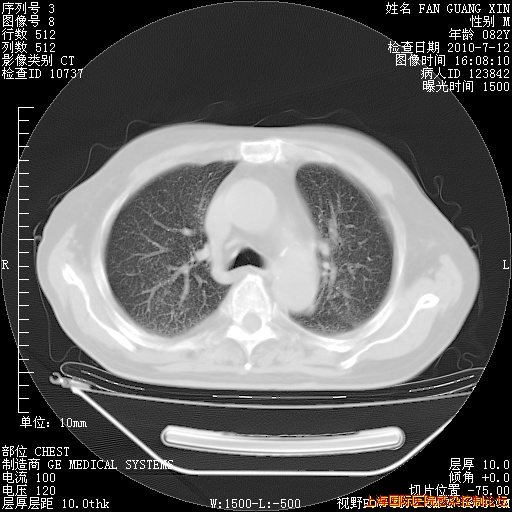

补发6月12日肺部CT肺窗

6月12日肺窗

整整相隔30天的肺部CT好像有所好转啊。甲强龙减量第3天,需要观察体温。